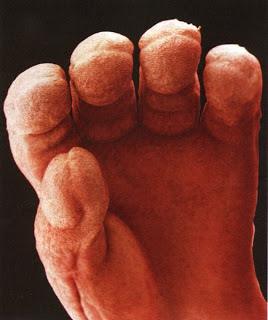

Սաղմի ձեռքը

16 շաբաթական պտուղն սկսում է օգտագործել ձեռքերը, որպեսզի ուսումնասիրի սեփական մարմինը: